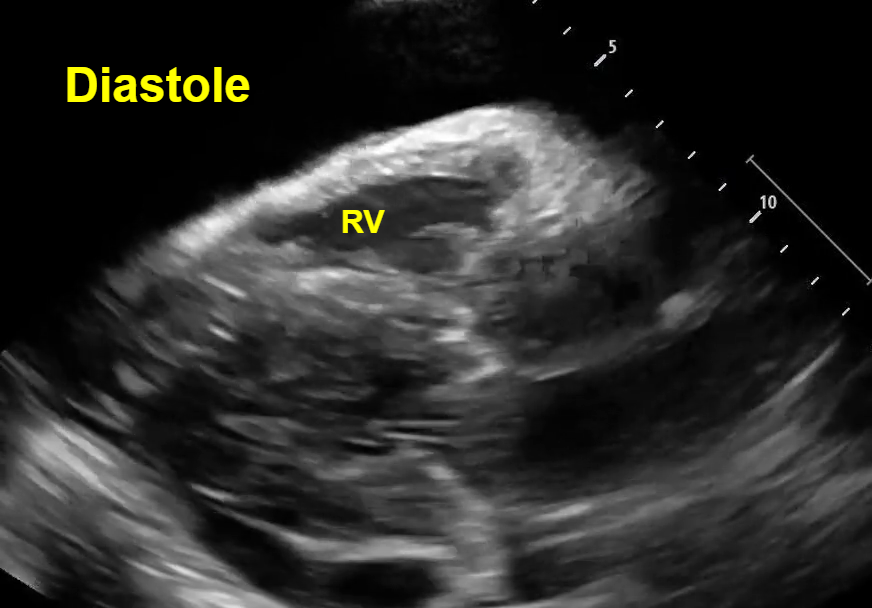

In both parasternal and short axis views seen above, there is a circumferential pericardial effusion surrounding the entire heart.

Short axis view: Here we see an example of ‘trampoline sign’, which is the characteristic bouncing motion of the RV. In the image above, we see inversion of the RV wall during diastole (arrow). How do we know this is diastole? Again, note that we can see the opening of the mitral valve in the LV when the RV wall inverts. See clip #2 to see a video of the ‘trampoline sign’.